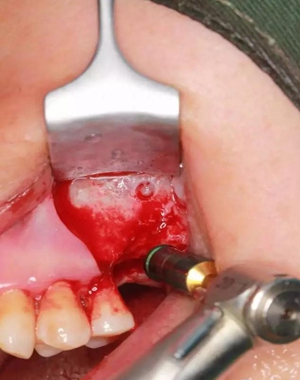

改良式外提升工具盒-外提 科貿(mào)嘉友收錄

大家好,我是梁老師的助理小依。由于梁老師每天手術(shù)檔期安排較滿,加上經(jīng)常出差講課,沒有時(shí)間整理病例 。為了方便大家更及時(shí)的了解梁老師最新手術(shù)動(dòng)態(tài),以后將由我為大家整理并推送梁老師最新經(jīng)典案例。案例文字旁白少,但圖片會(huì)盡量完整展示手術(shù)全過程,供大家學(xué)習(xí)參考。有任何問題,可以留言,梁老師會(huì)親自為大家解答。感謝大家對梁老師的支持和關(guān)注!